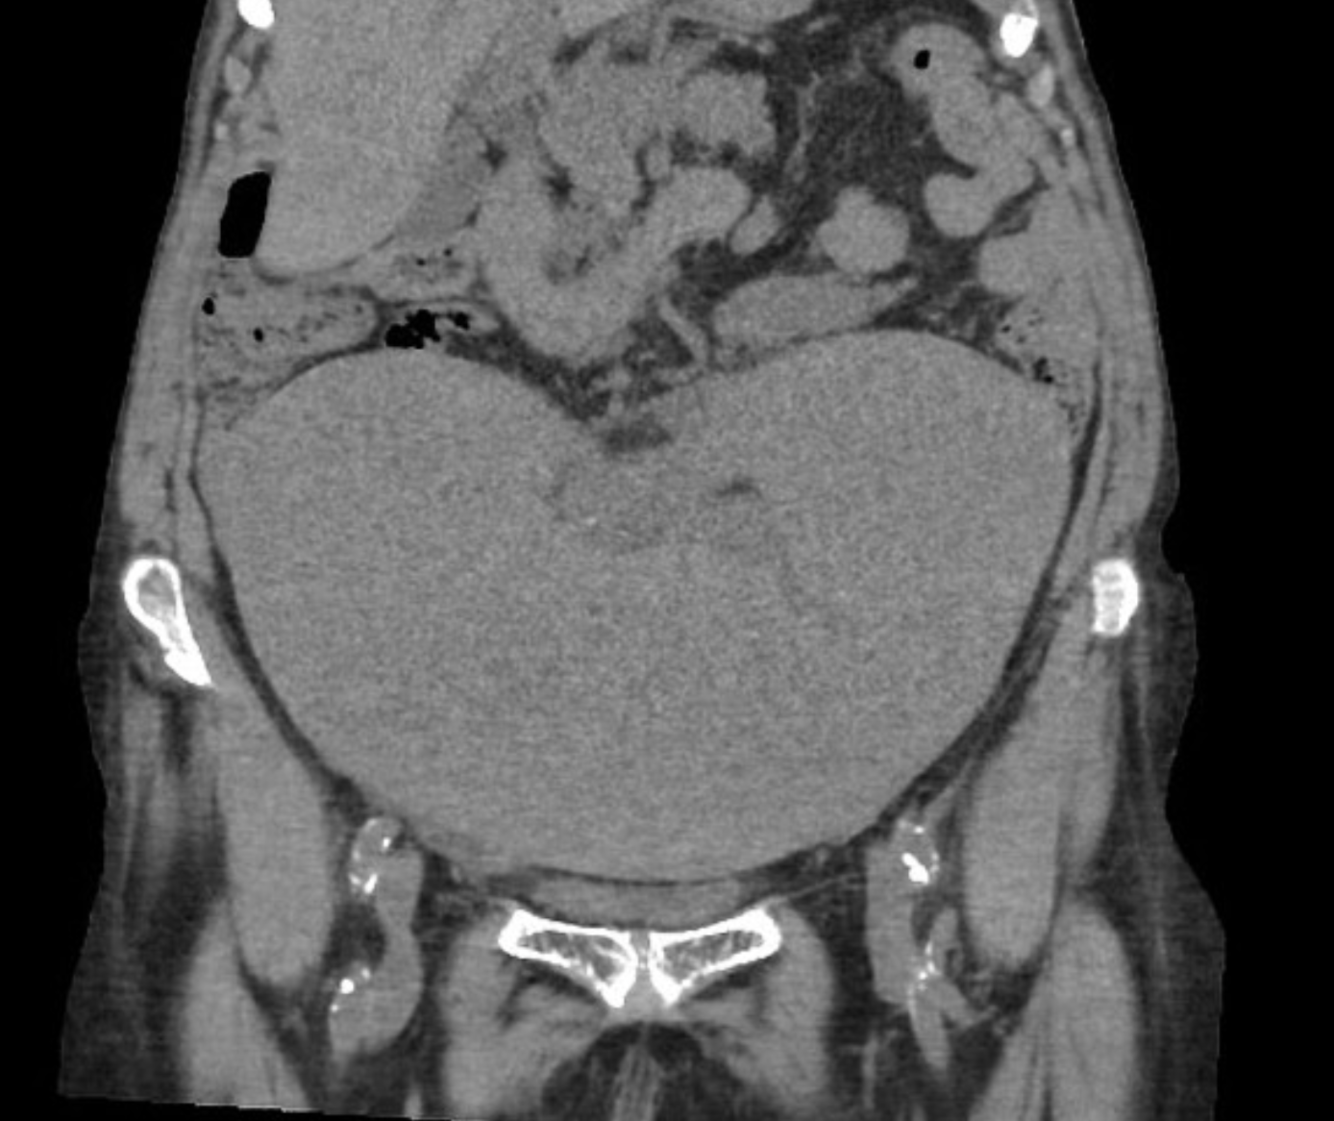

What are the causes of this condition?

The liver is at the upper limit of normal in size and her main portal vein is enlarged measuring 17 mm in diameter. The splenic vein is also enlarged. Focal fatty change is again demonstrated. No focal lesions. The remainder of the upper abdominal solid viscera are unremarkable, with no other infarcts identified. No lymph node enlargement and no focal osseous lesion.

Conclusion

Splenic infarcts is confirmed and presumably accounts of the patient’s presentation. The cause of the patient’s splenomegaly is uncertain, although the main portal vein and splenic vein do appear enlarged as does the liver raising the possibility of portal hypertension. Incidental adrenal adenoma.

Case Discussion

This case highlights the need to remember the differential of regional pain when assessing CT KUB for nephrolithiasis.